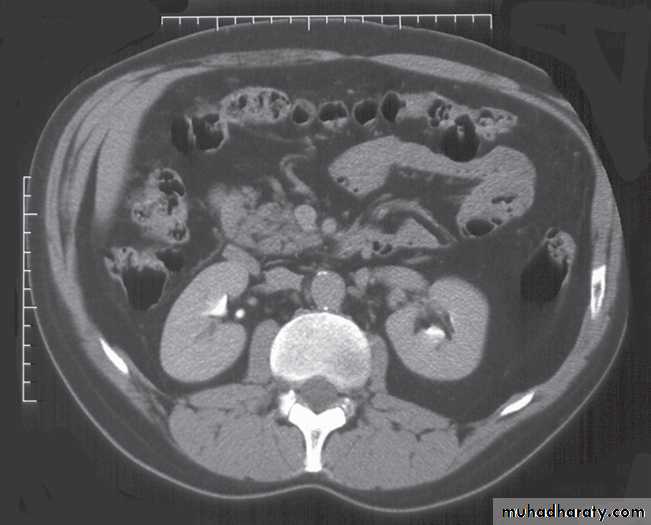

Computed tomography urography

CT is initially performed without intravnous contrast medium (non-contrast CT or ‘CT KUB’) to identify calcification .indication and include:

(i) The early renal cortical enhancement phase.(ii) The homogeneous nephrogramphase; and

(iii)The delayed urographic phase, obtained

several minutes later to demonstrate

contrast within the collecting systems.